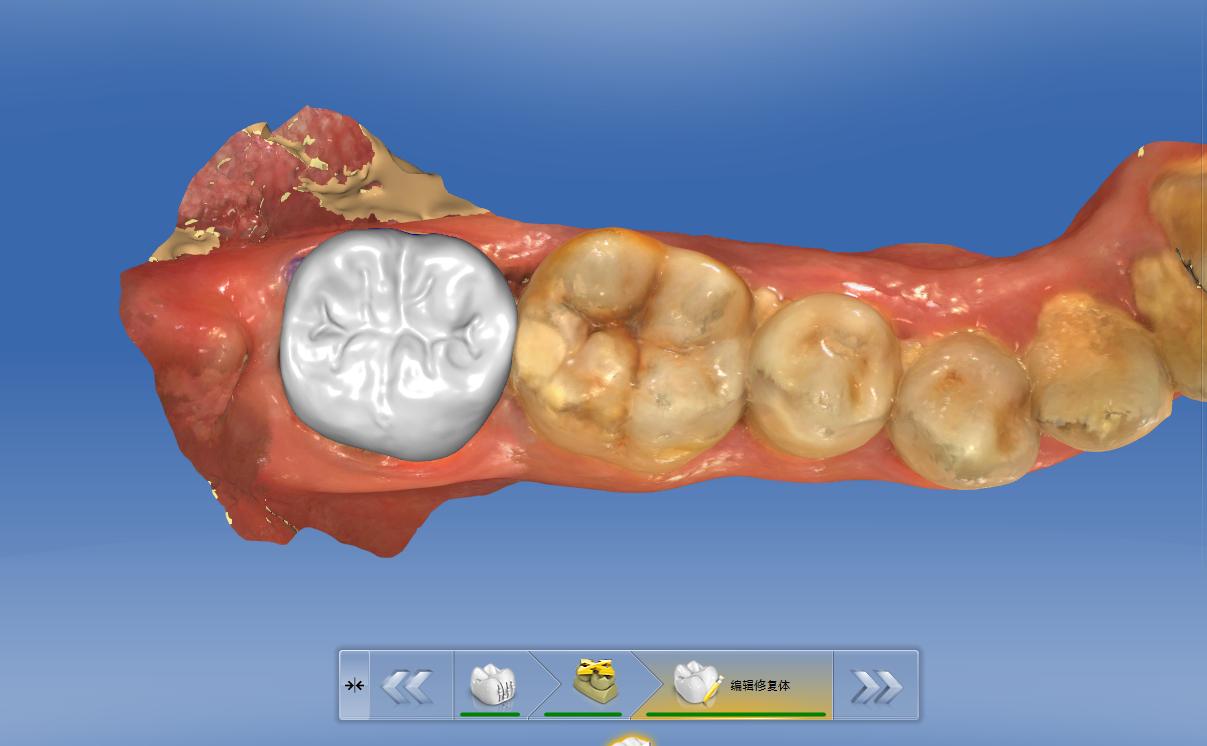

牙齿修磨后电脑光学扫描,得到精准的数字模型

CAD设计牙齿外形

因其通过电脑高精度的扫描,得到一个非常精确的数字模型,通过3D研磨打印的技术,制作出一个非常精确的修复体,通过高强度的粘接材料,将适合患者的修复体粘接在缺损的牙齿上面,恢复其功能及外观,从而延长我们坏了的牙齿的使用寿命。

CAM3D研磨打印,得到一个适合患者的牙齿修复体